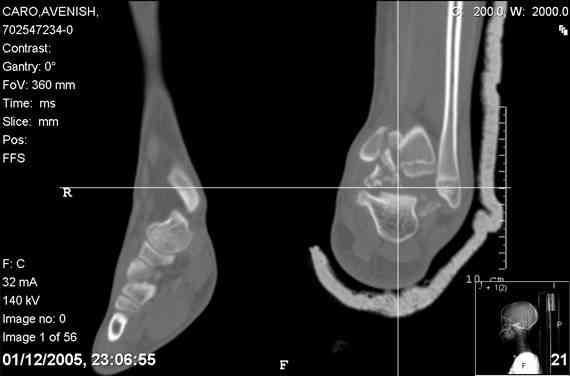

ya by popytalsya sobrat talus anatomichno,seichas pozdno operirovat iz za oteka,po etomy distrakziya apparatom budet optmalna.Posyalu vam podobyai moi sluchai.

14 years old girl

Fall from height ( 3rd floor)

Compressed fractures of L1-L2

Fx of orbital bone

He should have a CT scan prior to surgery.

Mark, судя по снимкам в день поступления произведен А.В.Ф., а остеосинтез ч-з какое время произведен?, остеосинтез произвели открытым способом?( на снимке п/о рубцы).

aparat postavlen v den postupleniya,rastaynuli, vpravili zakryto naskolko vozmoghno, a kogda otek spal sdelali otkrytoe vpravlenie.Teryat tut nechego, moghno tolko uluchshit.